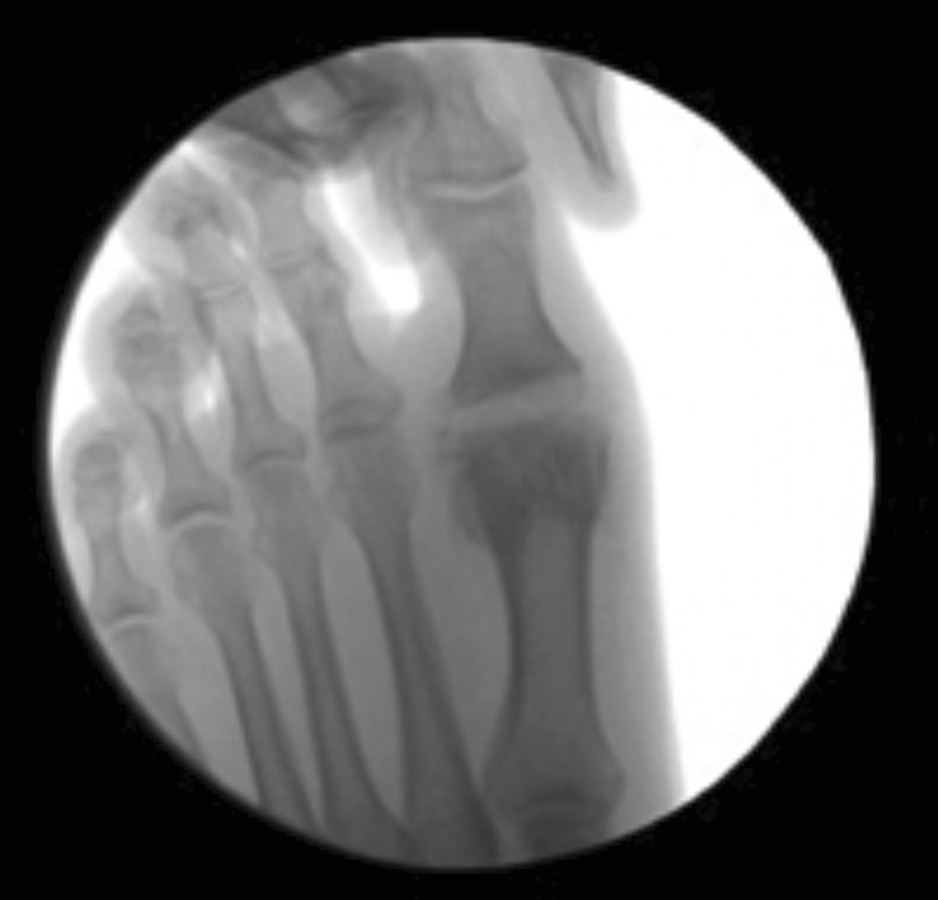

Se debe acceder a la articulación mediante 1 o 2 portales articulares situados a ambos extremos de la articulación a nivel dorsal (Figura 1). Deben ser unos portales un poco más grandes de lo normal, de 2 a 3 mm, que nos permitan un buen acceso a la articulación y poder extraer los fragmentos de cartílago que no podamos triturar. La fresa a utilizar es la Shannon® larga o Shannon® 44, que permite acceder a toda la articulación (Figura 2). En ocasiones, podemos utilizar la fresa de tipo pino (llamada así por su forma).

Figura 2. Cruentación de las superficies articulares con la fresa Shannon® bajo control radiológico.

Podemos hacer distracción del dedo para ir resecando fragmentos de cartílago, los cuales se extraen por el portal. Una vez resecado el cartílago, se cruentan las superficies articulares (Figura 3). La papilla ósea, al ser muy osteogénica, se deja en la articulación.

Figura 3. Distracción de la articulación. Superficies articulares preparadas para la artrodesis.